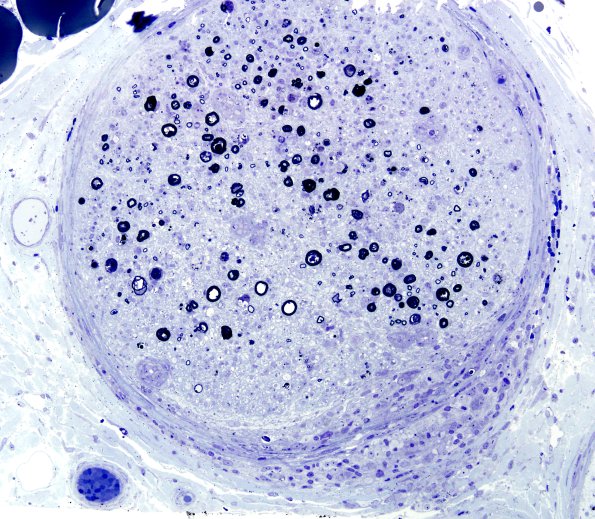

3B6A,B A focus of perineurial extension is accompanied by endoneurial small granulomas. (Plastic sections)